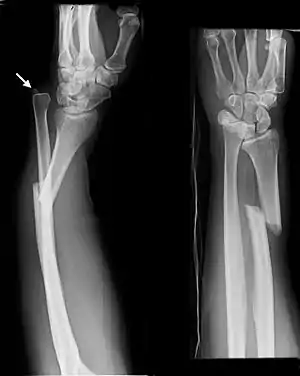

Galeazzi fracture

A fracture of the shaft of the radius can occur on its own, or be associated with disruption of the ulna-radial joint at the wrist, called a Galeazzi fracture.[2] A fracture of the radial head or neck with disruption of the ulna-radial joint at the wrist is called a Essex-Lopresti fracture.[2]

Front view of displaced fractured radius and ulna at wrist

Side view of displaced fractured radius and ulna at wrist

Front view of bowing fractured radius and ulna

Side view of bowing fractured radius and ulna